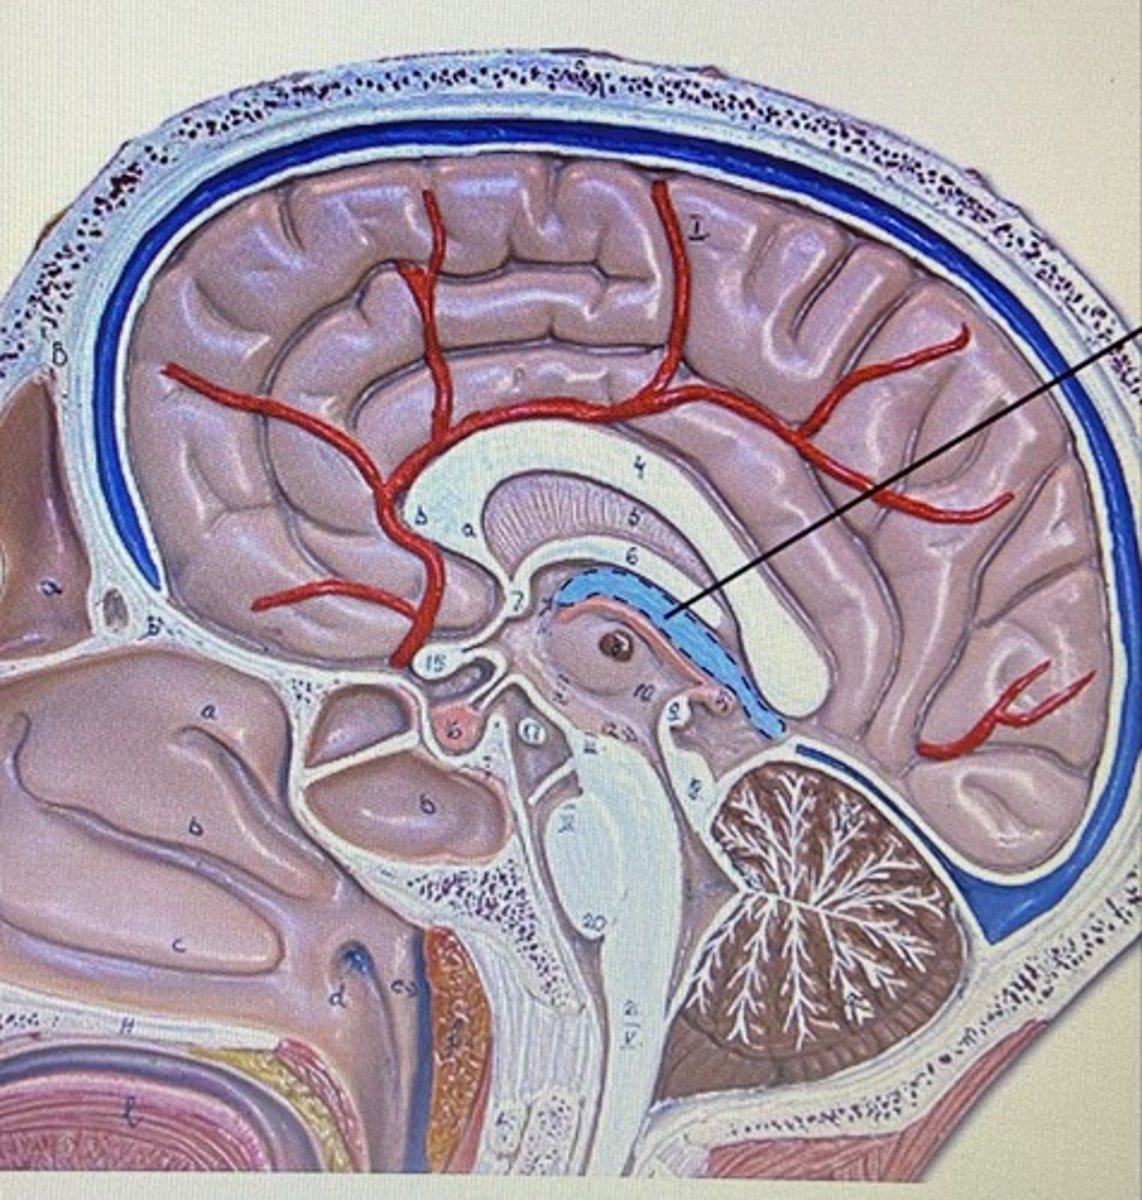

Corpus Callosum

Choroid Plexus

Fornix

Thalamus

Hypothalamus

Lateral Ventricle

Third Ventricle

Fourth Ventricle

Cerebral Aqueduct

Meninges

The three protective membranes

-dura mater

-pia mater

-arachnoid

Dura Mater

Arachnoid Mater

Pia Mater